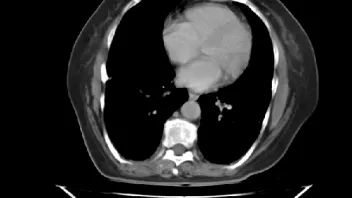

ist jemand unter Euch der sich auskennt mit CT Aufnahmen ?

Ich habe 3 Stück angehangen, sie stammen aus einem CT der Abdomen.

Möglich das es eine Serie eines Querschnitts darstellt Bild 1 zeigt den Start,Bild 2 eines aus den mittleren Aufnahmnen und Bild 3 das letzte dieser CT Serie.

Da ganz gezielt auf ein und die gleiche Stelle gehalten wurde mit sagenhaften über 80 Einzelaufnahmen interessiert mich brennend um die Darstellung welches Organges es sich bei diesen Aufnahmen handelt und ob darauf etwas bedenkliches eingekreist wurde.

Am Bett störte ich mich an zunehmenden, immer lauter werdenden Geräuchen, ein Geräuch als wenn man einen laut grollenden Wasserstrudel wahr nimmt, der durch ihren Körper tönte, immer lauter werdend. Da ich das nicht einordnen konnte fragte ich den Arzt und bekam folgende Antwort: "Der mensch bestünde ja zum Großteil aus Wasser. Im Sterbeprozess wäre das bei JEDEM so das man es laut wahrnimmt. Man müsse es sich so vorstellen das dieses Wasser immer mehr würde und aufsteigen würde bis in die Lungen die dann quasi davon außer Betrieb gesetzt würden und letzten Endes der Tod eintritt.Es wäre bei allen Menschen so die gehen und ich müsste mich nicht beunruhigen."